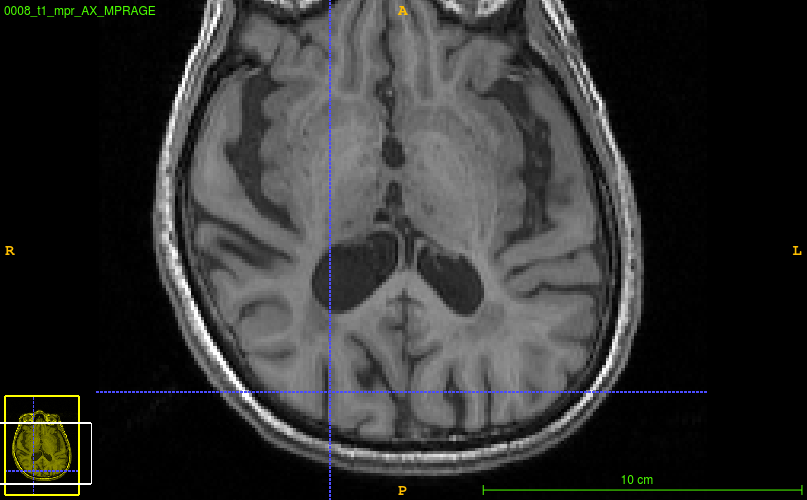

@cookpa it looks similar, in that it is estimating the entire gyrus as white matter

for example:   seems to be over-estimating white matter